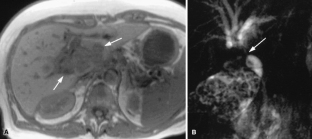

Usual and unusual causes of extrahepatic cholestasis: assessment with magnetic resonance cholangiography and fast MRI

Cholestasis may result from hepatocellular (intrahepatic) disease or biliary tract (extrahepatic) abnormalities. Etiologies causing extrahepatic cholestasis are extremely diverse and invasive procedures, such as endoscopic retrograde cholangiopancreatography (ERCP) and percutaneous transhepatic cholangiography (PTC), were previously required to establish the diagnosis. Due to refinements of magnetic resonance imaging (MRI) techniques, the patient with extrahepatic cholestasis currently can be evaluated noninvasively, and the information revealed frequently exceeds the findings obtained by ERCP and PTC. In this essay, we illustrate the classic MR cholangiographic (MRC) and MRI features of a variety of disorders causing extrahepatic cholestasis, including non-neoplastic disorders of the biliary tract (congenital abnormalities, infectious processes, iatrogenic disorders, and postsurgical complications) and neoplastic conditions (e.g., tumors of the pancreas, biliary tree, liver, ampulla, and regional lymph nodes). In most cases, familiarity with the key MRC features in addition to information obtained via cross-sectional MR images provide sufficient information for adequate lesion characterization.